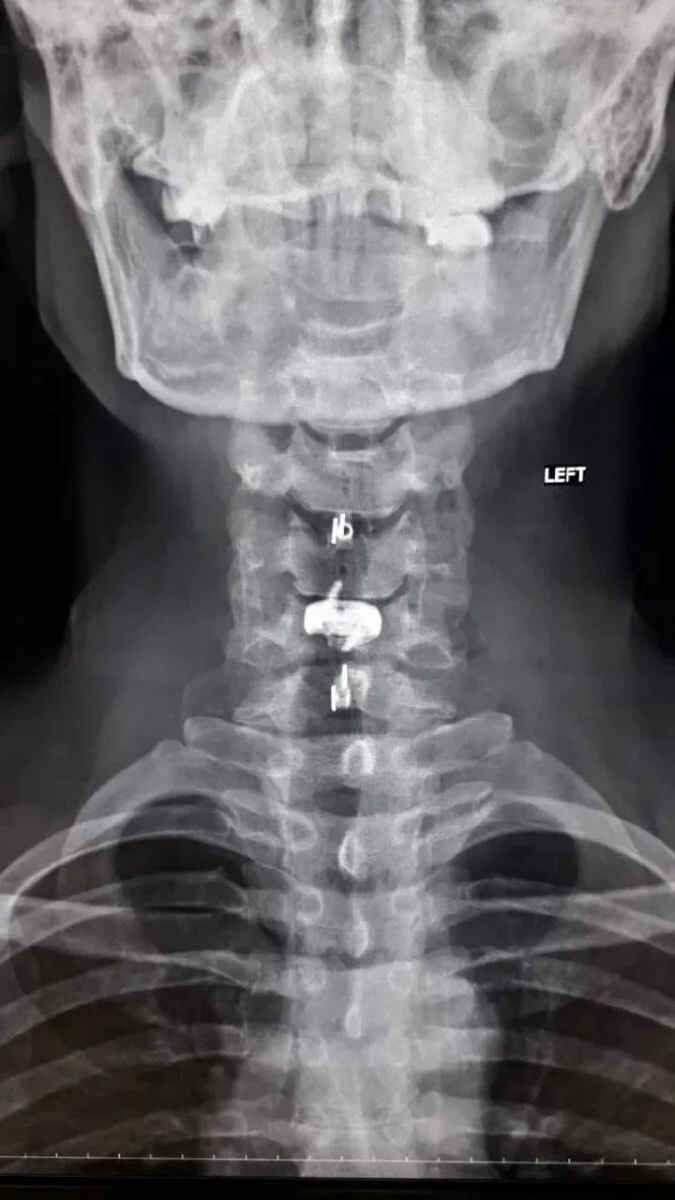

Нейрохирурги Воронежской городской клинической больницы скорой медицинской помощи №1 (БСМП №1) провели уникальную операцию 38-летнему пациенту, полностью восстановив ему свободу движений в руках. Команда под руководством заведующего отделением Павла Юрова устранила стеноз позвоночного канала, стабилизировала и укрепила шейный отдел титановыми конструкциями. Об этом сообщили в пресс-службе министерства здравоохранения Воронежской области 30 марта.

Мужчина годами мучился от остеохондроза шейного отдела. С августа 2025-го боль усилилась, распространилась на правую руку, добавив слабость и онемение. В стационаре мужчине поставили диагноз – диско-остеофитный стеноз позвоночного канала.

Результат операции впечатляет: уже через 3 часа пациент встал на ноги, не испытывал боли, а силы вернулись в мышцы. Мужчину выписали на 5-е сутки, но впереди его ждет реабилитация.